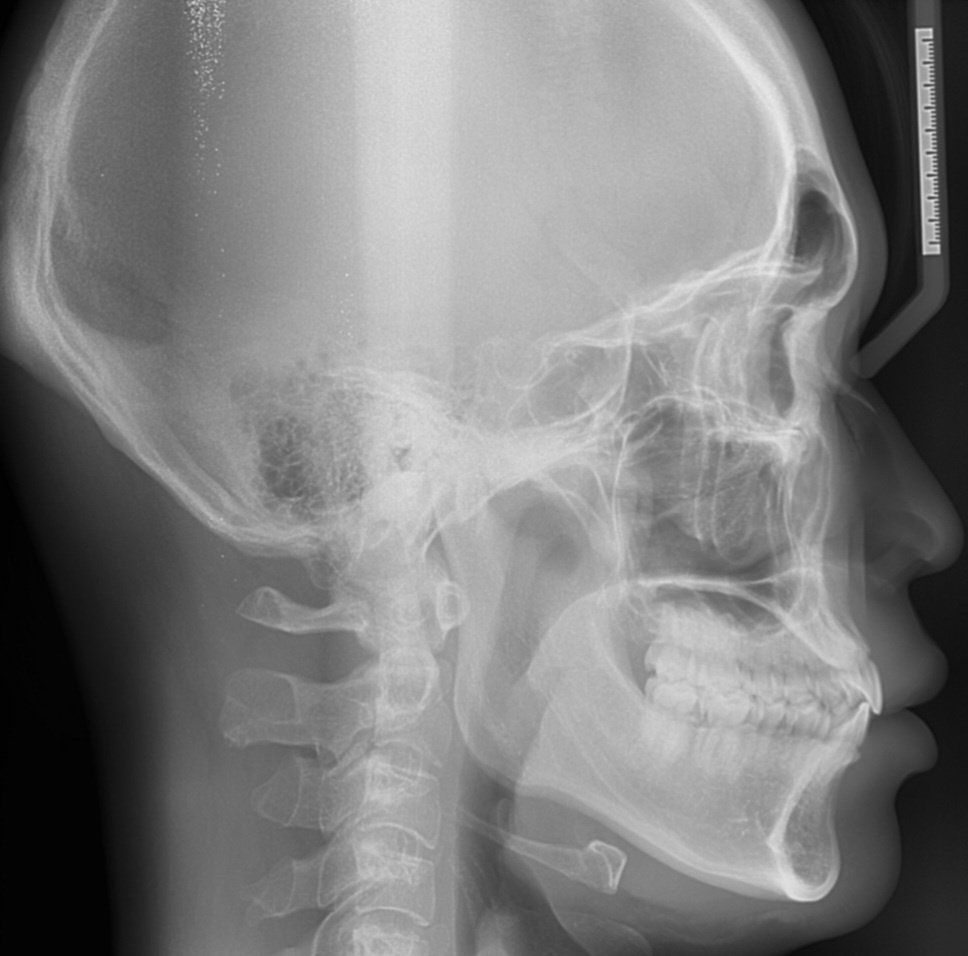

치과에서 하악골이 길다는데 얼마나 긴지 알수있나요?

1)치과 교정상담중에 하악골이 상악에 비해 길다는데 이게 얼마나 긴 건지 알 수 있나요?

2)치과선생님들마다 정밀상담결과가 다른 것 같은데 아하선생님들은 경험상 어떻게 평가하시는지 물어보고싶습니다. (어떤분은 3급부정교합 골격이다 어떤분은 정상범위이다, 아랫턱이 길다 평하십니다.)

3) 선생님들 경험 소견으로 제가 하악부근이 긴편에 속하나요??

1. 해당 정보를 알기 위해서는 계측점에 따른 수치가 필요합니다. 현재 ceph. 사진에 계측점에 따른 값이 나와 있지만 어느점을 기준으로 했는지에 따라 다르므로 계측을 직접해보아야 합니다.

2. 현재 수치만으로 보았을 때는 하악골이 과다하게 발달 한 것보다는 상악골이 덜 발달했을 가능성이 있어 보입니다.

3. 긴편에 속하지 않습니다. 상악골이 덜 발달 되어 길어보이는 것으로 보입니다.